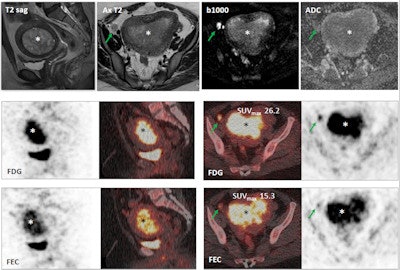

Images show a 29-year-old woman with stage IB grade 2 endometrioid adenocarcinoma filling the endometrial cavity (asterisks). There is intense uptake with FDG (26.2) and FEC (15.3). There is a lymph node (arrows), which shows on T2-weighted DWI (top row), as well as FDG-PET/CT (middle row) and FEC-PET/CT (bottom row). Images courtesy of Dr. Tara Barwick.

DWI was performed on a 1.5-tesla system with a torso phased-array coil. The FDG-PET/CT imaging protocol included a scan from the upper thighs to the skull base after four to six hours of fasting and FDG uptake of 60 minutes. The FEC-PET/CT exam was the same protocol as FDG-PET/CT and included the administration of 200 to 300 MBq of FEC.

Researchers then correlated information on tumor grade, primary tumor FDG maximum standardized uptake values (SUVmax), FEC SUVmax, and the apparent diffusion coefficient (ADC) mean for DWI. Histology was used as the reference standard.

One experienced reader interpreted both the FEC- and FDG-PET/CT images. Cervical and endometrial tumor volumes of interest were defined by segmentation of 40% SUVmax threshold. For DWI, primary cervical and endometrial tumors were segmented on the ADC map correlating with the T2-weighted and b = 1200 images at each slice where a tumor was present.